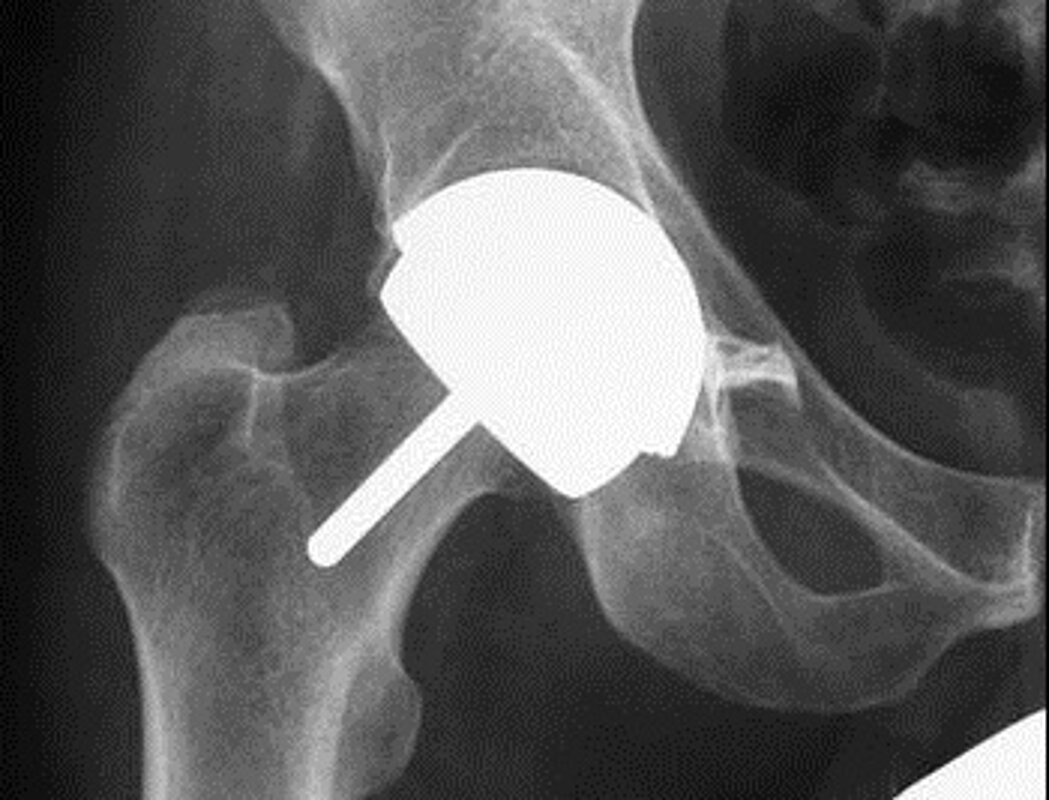

In Deutschland werden jährlich rund 400.000 Hüft- und Knieendoprothesen bei Menschen mit starkem Gelenkverschleiß oder nach Brüchen eingebaut. In Amerika stieg laut der „Organization for Economic Cooperation and Development“ die Anzahl des Hüft- und Knieersatzes zwischen 2000 und 2009 um 25 Prozent an. „Wenngleich Deutschland bereits an der Spitze der Versorgung in Europa steht, ist ein neuerlicher Anstieg auch in Deutschland zu erwarten. Einer der Gründe dafür ist die demografische Veränderung. Der Versorgungsbedarf wird künftig stark steigen, denn die jetzt 50-jährige Babyboomergeneration wird von Volkskrankheiten wie der Gelenkarthrose nicht verschont bleiben“, so Niethard. Zudem geht die alternde Gesellschaft mit einem Anstieg von Altersbrüchen einher. „Wir rechnen mit einer Verdopplung bis Verdreifachung von Altersbrüchen in den kommenden 20 Jahren, so dass auch die Anzahl der Frakturendoprothesen nach osteoporose-assoziierten Hüftgelenksfrakturen steigen wird“, sagt Professor Reinhard Hoffmann, Generalsekretär der Deutschen Gesellschaft für Unfallchirurgie (DGU).

Um den wachsenden Bedarf bei der Endoprothesenversorgung durch die demografische Entwicklung zukünftig abdecken und sichern zu können, treibt die DGOU verschiedene Qualitätssicherungsmaßnahmen voran. Dazu gehören die innerärztlichen Initiativen wie das Endoprothesenregister der Deutschen Gesellschaft für Orthopädie und Orthopädische Chirurgie (DGOOC), das AltersTraumaZentrum DGU® der Deutschen Gesellschaft für Unfallchirugie (DGU) sowie auch die Förderung des ärztlichen Nachwuchses im Fach Orthopädie und Unfallchirurgie.